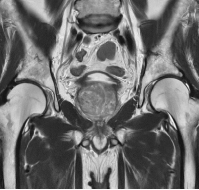

MRI検査

男性器領域

- 前立腺

- 前立腺がん・前立腺肥大など

- 膀胱

- 膀胱がんなど